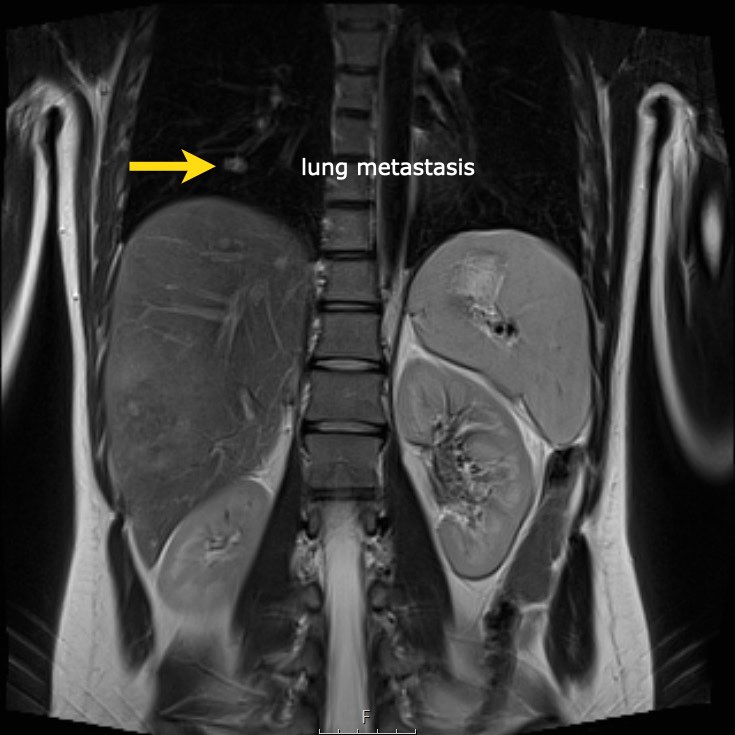

Hình ảnh

U nguyên bào thận ở thận trái của bé trai ba tuổi. Phần còn lại của thận trải dài trên khối u (dấu hiệu “móng vuốt” mũi tên). Khối u khá đồng nhất với một số vùng nang.

Continue with the MRI.

U nguyên bào thận ở thận trái của một bé trai ba tuổi. Khối u thùy đôi nằm ở vùng cực giữa. Có một đài thận giãn ở cực trên (mũi tên).

Một bé gái ba tuổi có khối u thận trái và huyết khối khối u lớn trong tĩnh mạch thận và tĩnh mạch chủ dưới. Có di căn gan (phát hiện không thường gặp) và di căn phổi.